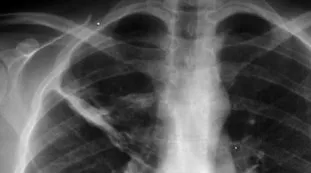

effetti collateraliAllarme dei medici, le pillole per la pressione "aumentano il rischio di tumore ai polmoni"4 febbraio 2020